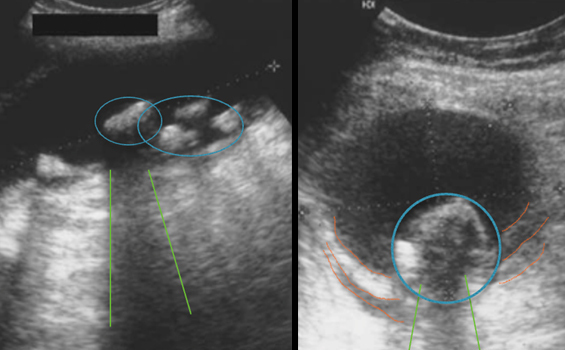

Il s’agit d’une image typique de cholécystite aiguë lithiasique sans signe de complication.